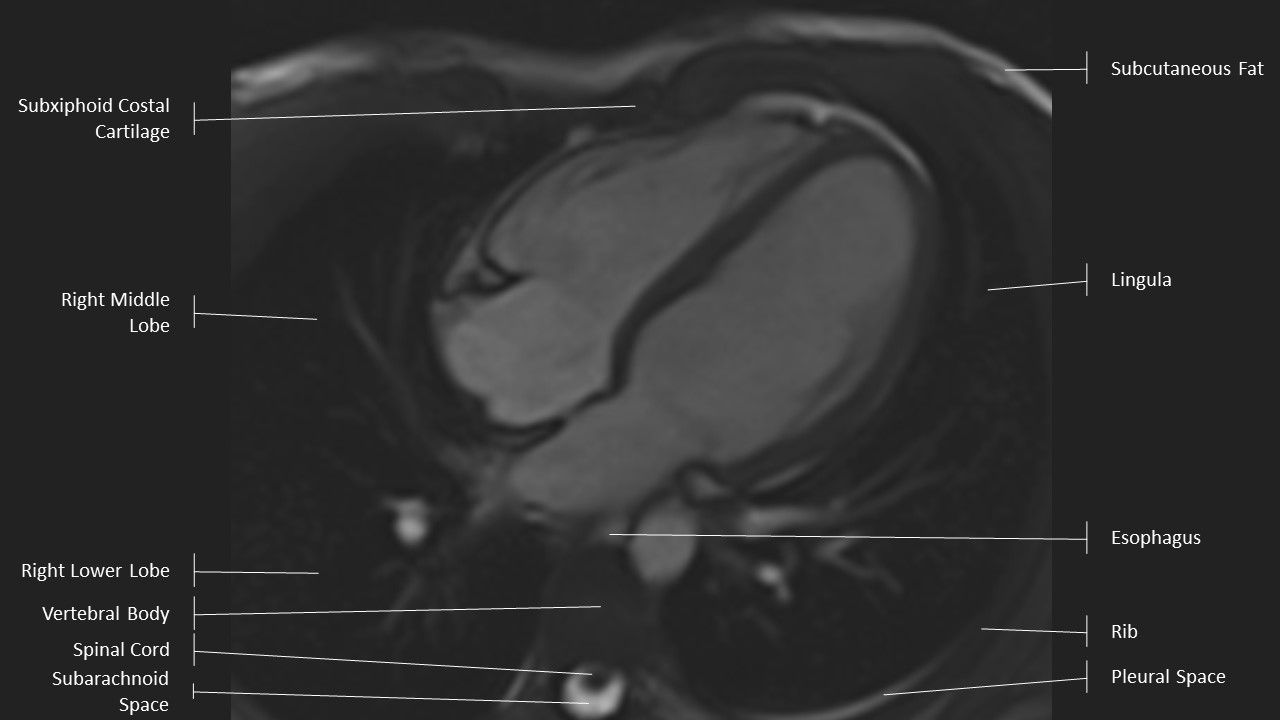

4 Chamber View